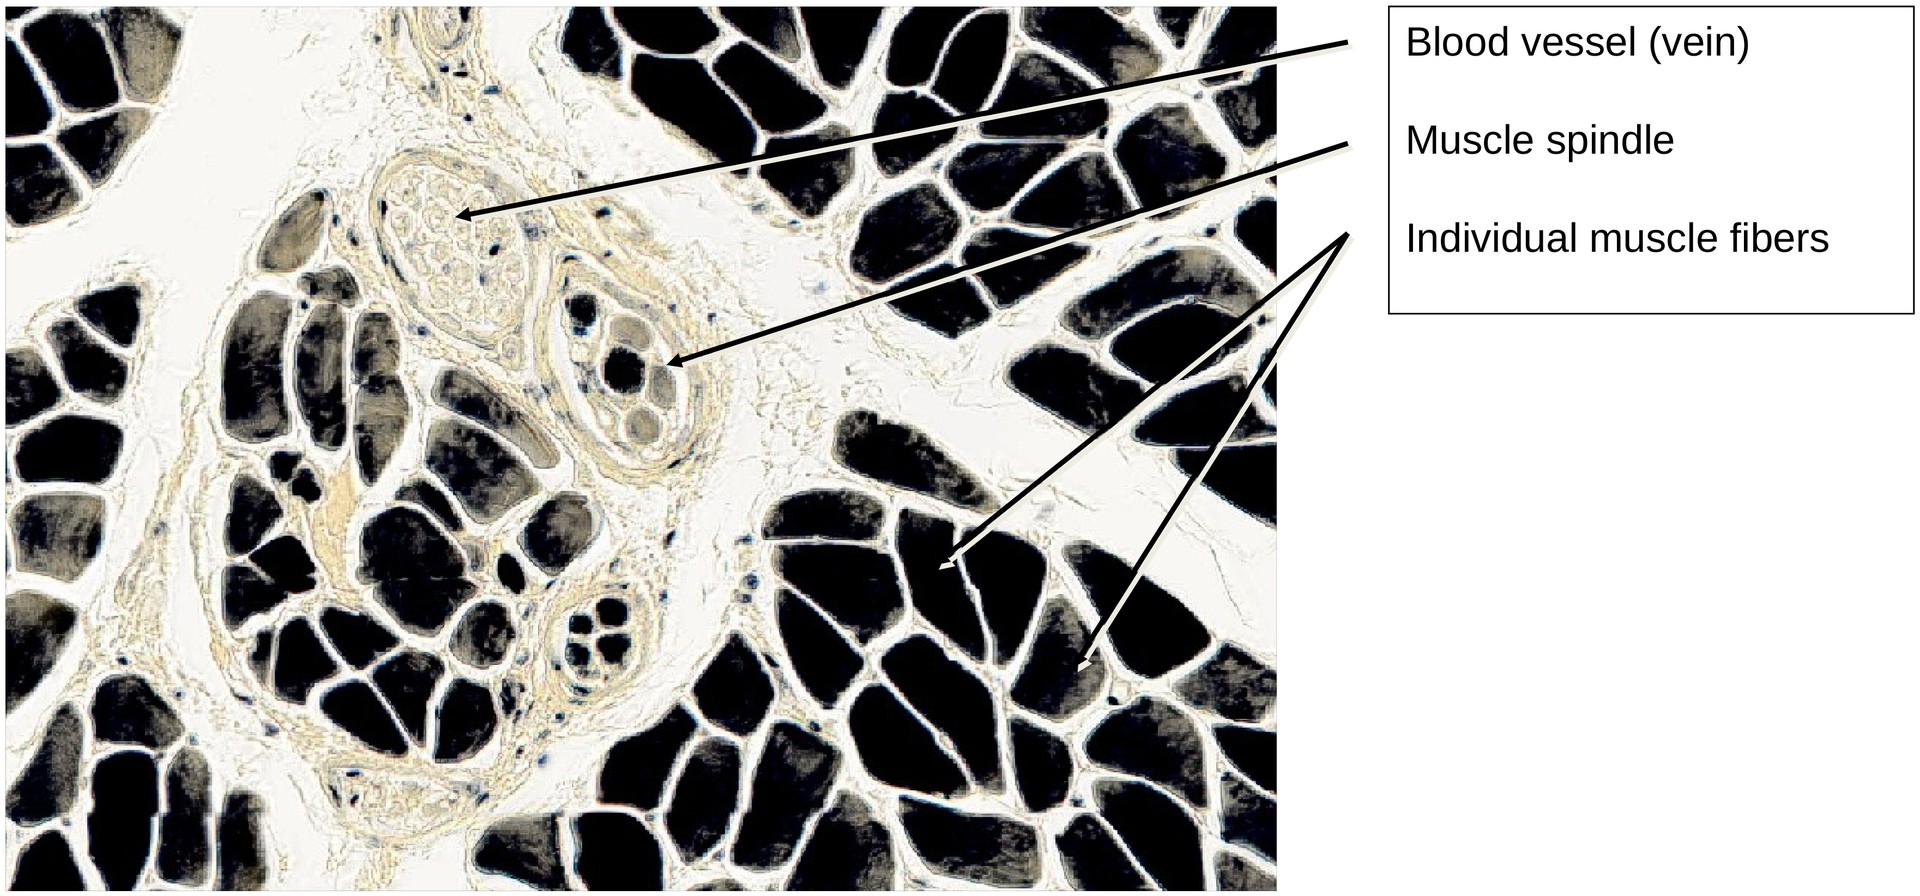

Skeletal muscle, transverse section (neck muscle)

Iron hematoxylin stains primarily the cell nuclei and myofibrils. Differences in staining intensity are unavoidable during differentiation and are partly due to variations in enzyme content among the fibers, as well as fixation-dependent differences.

In cross-section, the muscle is subdivided by connective tissue strands into coarser and finer bundles of muscle fibers:

Perimysium – connective tissue surrounding groups of muscle fibers.

External perimysium (perimysium externum): surrounds secondary bundles.

Internal perimysium (perimysium internum): surrounds primary bundles.

Endomysium – fine connective tissue enveloping individual muscle fibers.

Within the perimysium, arteries and veins of various calibers can be observed, sectioned in different planes depending on their orientation.

Muscle fibers appear as polygonal profiles in cross-section. Once a fiber containing a nucleus is located, the position of the nucleus can be determined relative to the sarcolemma (typically subsarcolemmal, or hypolemmal).